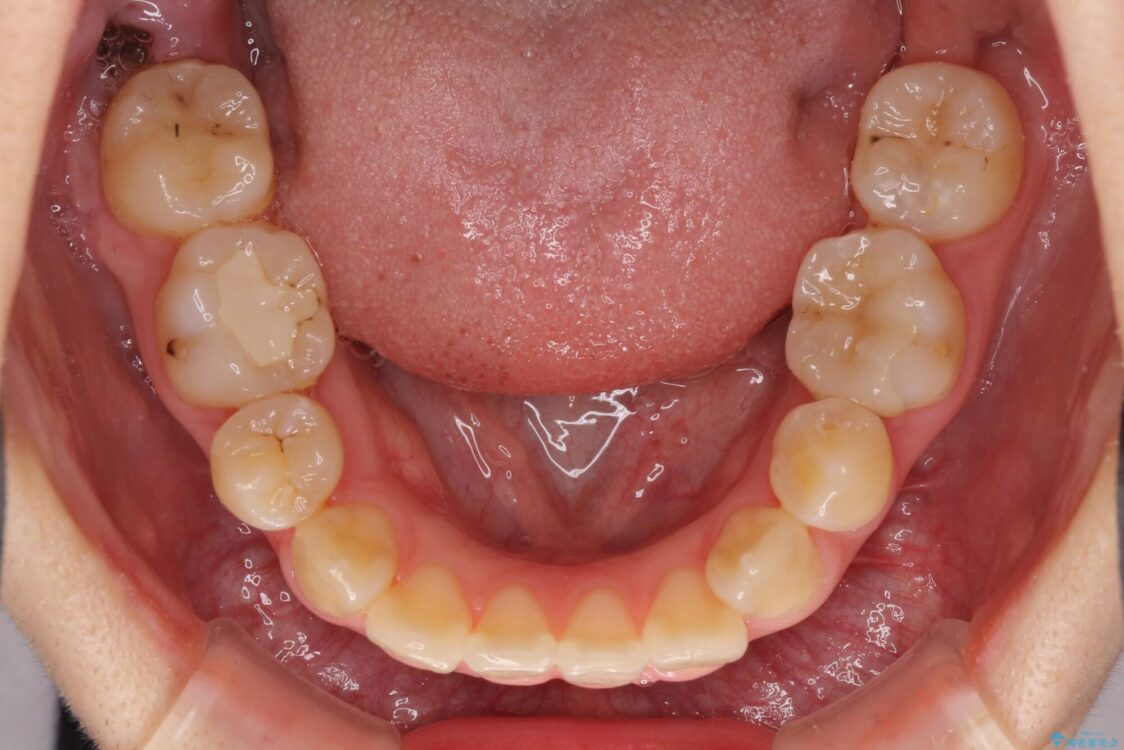

治療前

• 虫歯治療ついでに歯並びの後戻りを改善 インビザラインによる矯正治療 治療前画像